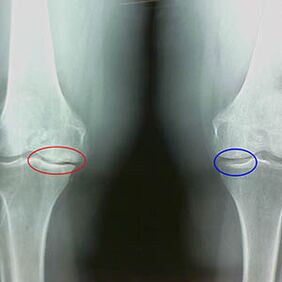

La détermination du degré d'arthrose se produit par x-rayonsrévélant la participation au processus pathologique des structures osseuses. Son changement indique que le système musculaire est dans un déséquilibre depuis 5 à 10 ans. En règle générale, les gens Dolores Dolores Expérience pendant plusieurs années.

Caractéristiques initiales de la rayon x de la deuxième étape de l'arthrose du genou:

- Les bords pointus des tubercules interceptifs dans le tibia, où le ligament est rejoint sous la forme d'une croix;

- rétrécissement de l'écart articulaire du côté médial;

- Les bords pointus des condiles des os sur les côtés médiaux, moins fréquemment sur le côté, selon le développement de la valgo ou la déformation de l'articulation diversifiée.

Pour la deuxième étape de Larsen Le rétrécissement de l'écart articulaire dans plus de 50% est caractéristique, mais cela ne peut être vérifié que dans la dynamique ou la comparaison avec une articulation différente.

La radiographie montre la présence d'ostéophytes, un changement d'espace entre les os fémoraux et chauds, indiquant la perte de cartilage dans le genou. Parfois, la ligne X des articulations du genou montre des signes d'usure de cartilage importants, mais les patients ne ressentent pas de douleur significative.Au contraire, l'arthrose de la première étape peut interrompre la fonction du genou, puisque la cause de la douleur est les muscles hypotoniques.